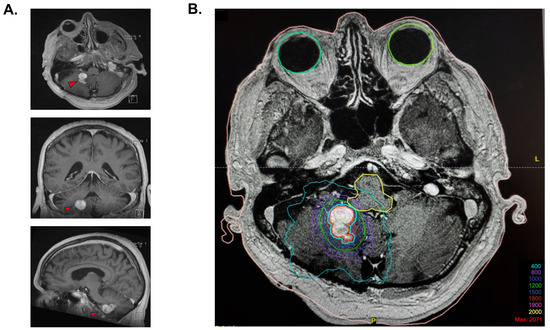

In 2007, a 2 cm progressing enhancing lesion was found, which was stable throughout 2008 and 2009. Minimal progression was again noted in 2010 and 2012. In September 2014, the enhancing portion of the lesion was noted as progressing from 19 × 12 × 15 mm to 20 × 15 × 16 mm (anteroposterior, transverse, cranio-caudal, respectively). A de novo circular, fluid-filled lesion was also noted anteriorly, measuring 8.1 × 15.2 × 13 mm. At the time of radiosurgery planning, the overall lesion measured 25 × 15 mm (AP, T, respectively), with the presence of solid as well as fluid components (Figure 1A).

Radiosurgery for the slowly progressing lesion was recommended at the neuro-oncology tumor board, primarily because of the deep location of the lesion and its relapsing nature. The procedure took place on 17 December 2014. Immobilization was performed using a stereotactic frame, and an axial MRI T1 post-gadolinium sequence was fused to the planning CT scan for delineation of the target. A dosimetric plan was obtained using the X-Knife treatment planning system. SRS was delivered on a Varian Trilogy unit equipped with a high-definition multi-leaf collimator. The patient received an SRS of 18 Gy, which was prescribed at the 87% isodose, considering that the lesion was situated at millimetric distance to the brainstem to optimize the dose fall-off (Figure 1B). A total of 83% of the tumor volume was covered by the 18 Gy isodose, and 99.9% was covered by the 15 Gy isodose. The gross tumor volume (GTV) was 3.77 cm3. The treatment volume ratio (TVR) was 1.2, and the prescription isodose to target volume (PITV) was 1.0. The maximal point dose to the brainstem was 13.1 Gy. The volume of normal brain that received 12 Gy was 7.9 cm3.

Figure 1. Stereotaxic radiosurgery planification. (A) Cerebral MRI T1 images prior to stereotactic radiosurgery, with a demonstration of the polylobulated lesion in the axial view, coronal view, and sagittal view. (B) Isodose coverage of the GTV (in red) for the 18 Gy radiosurgery plan. The blue contour is an expansion of 1 mm of the GTV treated at an 87% isodose because of the proximity with the brainstem. A total of 83% of the tumor volume was covered by the 18 Gy isodose, and 99.9% was covered by the 15 Gy isodose.